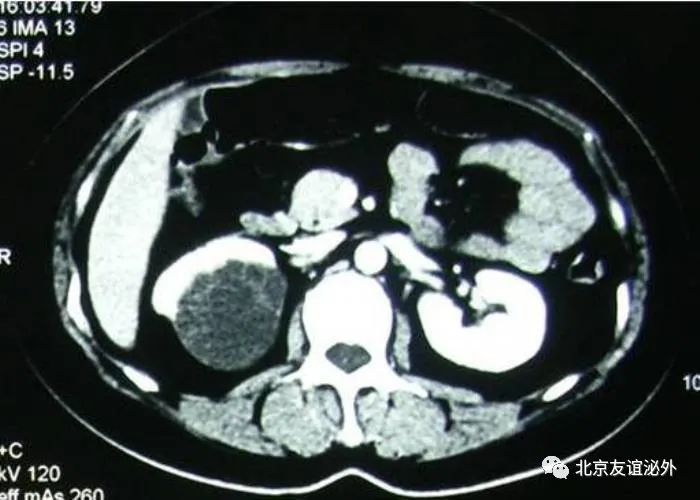

图1. Bosniak I级良性囊肿,是临床上最常见的囊肿